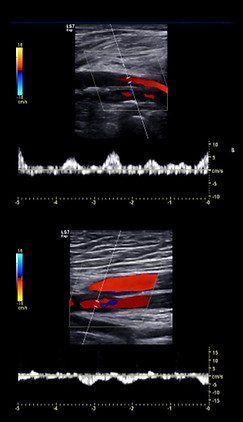

Estudio de arterias, venas y circulación (Doppler color-HD)

El ultrasonido Doppler venoso es un estudio de imagen no invasivo que permite evaluar el flujo sanguíneo en las venas de las piernas, brazos u otras partes del cuerpo.

A través de ondas de sonido de alta frecuencia, este estudio genera imágenes en tiempo real del sistema venoso, ayudando a detectar problemas como:

Proporciona imágenes en tiempo real del flujo de sangre en las venas

Permite ver si la sangre fluye en la dirección adecuada y con la velocidad correcta

En el Doppler, además de la imagen, se observa el flujo sanguíneo, su velocidad y dirección.